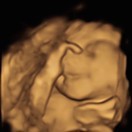

อ่านเพิ่มเติม18กันยาคะ ซาวล่าสุดเป็นตัวแล้ว เจอรก แขน ขา หู ตา จมูกปาก หัวใจเต้นตุ้บๆ ดิ้นเก่งดิ้นแรงมากคะ